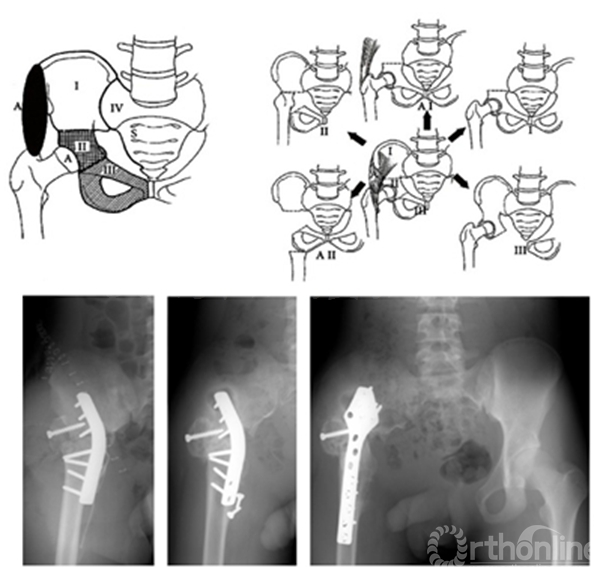

髋臼肿瘤多为髂骨或耻坐骨连同髋臼同时受到肿瘤的破坏。累及髋臼的骨盆肿瘤切除、重建是具有挑战的手术,各类假体置换是主要治疗手段,主要包括组配假体,个体化定制假体,3D打印假体,“冰淇淋杯”假体;复合或不复合异体骨移植等。

生物重建技术主要包括髋关节旷置术、髋关节移位术、髋关节融合术。

骨盆肿瘤髋关节旷置术

骨盆肿瘤髋关节旷置术1978年由Steel等报道。报道称骨盆肿瘤髋关节旷置术操作相对简单;创伤小,并发症少;功能改善情况患者可以接受。